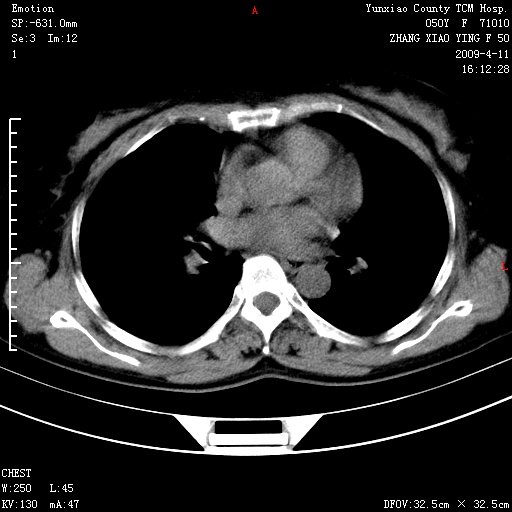

标题: CT19324:胸闷1周伴咳嗽 [打印本页]

标题: CT19324:胸闷1周伴咳嗽

病灶周围肺纹受压移位走行较柔和,余肺里实质均匀,纹理如常,肺间质无显著纤维化,支持考虑孤立性肺囊肿

考虑右肺中叶肺囊肿。